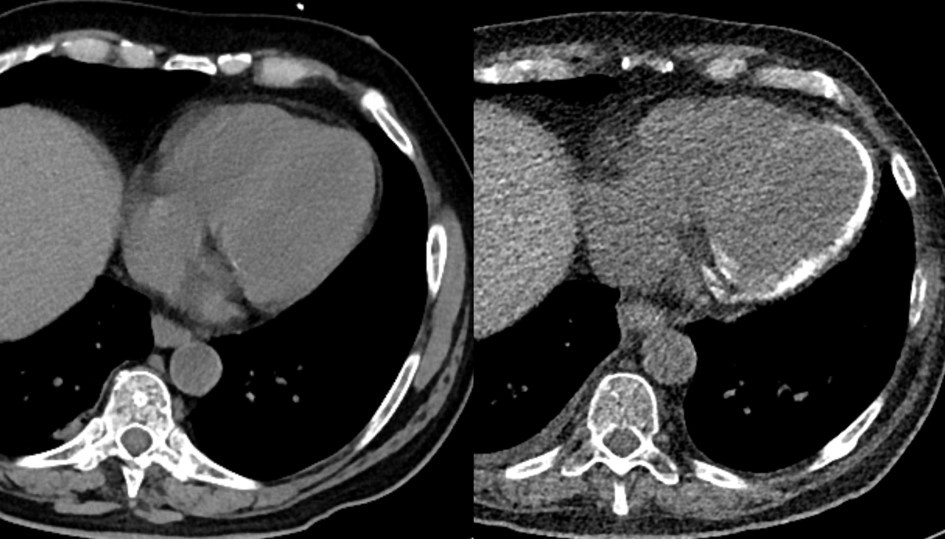

The reported case shall highlight severe sepsis as possible cause of myocardial calcification, as well as the highly dynamic development thereof within a time span of merely 10 weeks. A 60-year-old male patient had been admitted to hospital for palliative therapy of progressive multiple myeloma, which lately had transformed into plasma cell leukemia. After commencing his third therapy cycle with Elotuzumab, the patient suffered from a pneumogenic sepsis due to staphylococcus infection that required mechanical ventilation for 7 days. Antimicrobial therapy followed antimicrobial susceptibility testing and included Tazobactam, Piperacillin, and Fosfomycin. During his hospital stay, computed tomography images of the chest were acquired initially, i.e. at onset of pneumogenic sepsis (Figure 1.: left panel), as well as after 10 weeks (Figure 1: right panel) to follow-up pneumonia consolidations in both upper lung lobes. Surprisingly, non-contrast enhanced follow-up CT images revealed newly developed calcifications within the outer myocardial layers of the left ventricle.

Figure 1.Non-contrast enhanced CT scans of the chest initially during onset of pneumogenic sepsis (right) and after 10 weeks (left) show rapid development of non-preexisting, extensive myocardial calcifications.